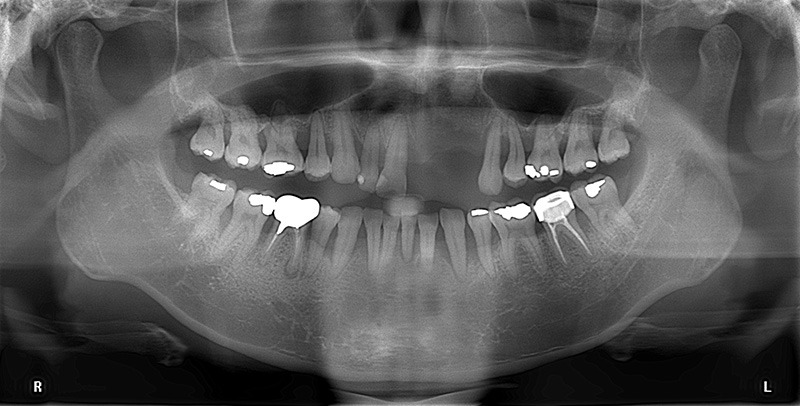

台北胡先生因為長期抽菸的關係,導致他年紀輕輕就面臨嚴重的牙周問題。他的口腔狀況十分嚴峻,口內幾乎所有牙齒都鬆動,甚至因此導致左上二顆門牙缺牙。這不僅影響了他的外貌,使他總是不敢開口大笑,連吃東西時也無法細嚼慢嚥,經常胃痛。

經由廖醫師的全方位評估,為胡先生訂立了一個完整的全口重建計畫,治療計畫共分為三個階段,從全口矯正及牙周治療,再到牙周齒槽骨重建手術(補骨),循序漸進,最後完成人工植牙和全瓷冠,順利恢復他的口腔健康。

首先,我們採隱適美隱形矯正來調整胡先生牙齒的位置和咬合狀態,同時也為他進行牙周病治療,處理牙周組織的健康問題,確保整體齒列與牙周環境適合後續的治療。

牙周病患者在植牙前須先做好牙周治療,將牙周控制在健康的狀況下再進行植牙,減少日後植牙掉落失敗風險。

經過初步的矯正與牙周病治療後,我們進入最關鍵的第二階段:重建牙周齒槽骨──也就是常聽到的「補骨手術」。

這是一項複雜的手術,我們針對左側上顎的門牙至第一大臼齒的區域進行了大範圍的水平和垂直骨增生手術,並覆蓋鈦網維持骨頭生長所需要的空間,待牙齒周圍骨質恢復穩定,為後續的植牙治療奠定堅實基礎。

完成補骨手術,待齒槽骨生長到足夠的寬度和高度後,我們便為胡先生進行人工植牙手術,分別在上顎左側正門牙和側門牙缺牙處植入人工牙根。同時,我們也進行了相應的牙周支持性治療,以確保新植入的植體有更好的支撐和保護。

待植體與骨頭緊密結合後(骨整合大約需要4~6個月的時間)在植體上安裝全瓷冠假牙,使他的新牙看起來自然美觀。